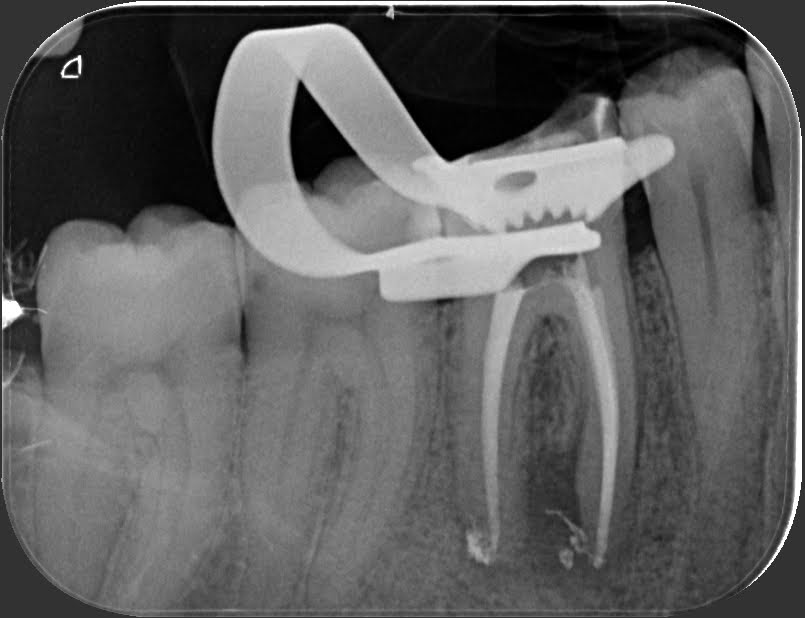

ENDODONZIA

Caso clinico – ritrattamento ortogrado di 1° molare inferiore con lesione

Caso clinico – trattamento ortogrado di 2° molare inferiore